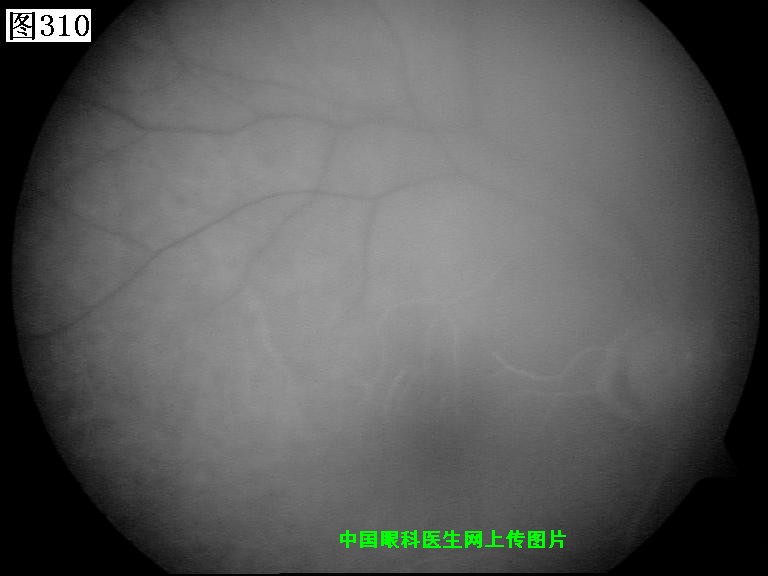

309 310 311 312